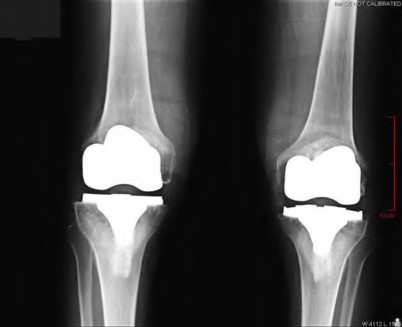

A 64-year-old woman with osteoarthritis underwent bilateral total knee replacement 3 years ago. Current radiographs are shown in Figure A. She reports a 3-month history of bilateral knee pain while at rest and increasing swelling in the knees. Her ESR and CRP are elevated and bilateral knee aspiration cultures reveal Staphylococcus aureus. What is the most likely outcome if the patient undergoes simultaneous, bilateral knee resection arthroplasty with cement spacer and a course of intravenous antibiotics?

This patient presents with bilateral total knee arthroplasty infection.

Wolff et al report Level 4 evidence of 18 patients followed an average of 5 years after bilateral TKA infection. Eleven patients were initially treated with attempts to salvage the original prosthesis (polyethylene l liner exchange, I&D, IV antibiotics and chronic oral suppressive antibiotics. With prosthesis retention, 9/11 (81%) developed recurrent infection at a mean of 15 months. The other 10 patients initially underwent resection arthroplasty with cement spacer and a course of IV antibiotics. Seven of the 10 (70%) underwent reimplantation at a mean of 3 months (6 weeks to 5 months) and none of the patients required revision at mean of two years follow up. Satisfaction rates were significantly higher among this group of patients. The authors advocate the protocol of bilateral TKA resection arthroplasty with cement antibiotic spacer and course of IV antibiotics followed by prosthesis reimplantation.